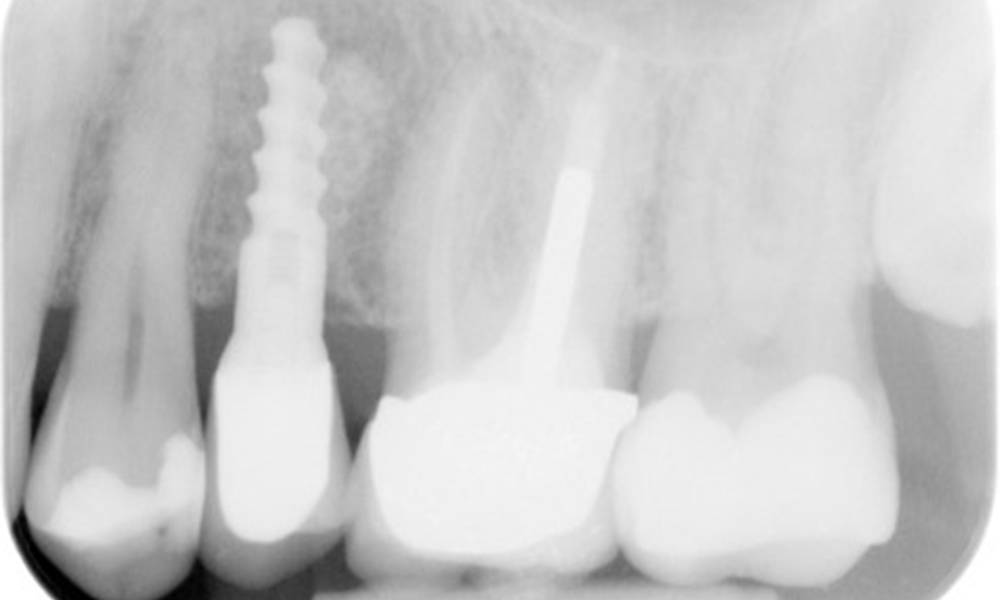

В медицинската история 55-годишният пациент заявява, че няма хронични заболявания и не приема никакви лекарства. Начинът на живот на пациента също е без забележки. Пациентът има няколко зъбни възстановявания и два импланта (2-ри и 4-ти квадрант). Въз основа на настоящите данни се установява гингивит при иначе стабилно пародонтално състояние върху редуцирания пародонт (стадий III, степен А).

Пациентът не показва особени рискови фактори със специфични дентални последици. Следователно ключовият фактор е изискването по отношение на оралното здраве. В това отношение доброто орално здраве се проявява при стабилен, редуциран пародонт. Ако при контролен преглед се установят данни за увеличаване на дълбочината при сондиране в сравнение с изходното ниво, съчетано с дифузно кървене, следва да се предприеме диагностика с помощта на рентгенова снимка (дентален рентген), за да се установи загуба на периимплантатна кост на ранен етап и да се предприемат съответните интервенции.

OPG: 29/02/2024